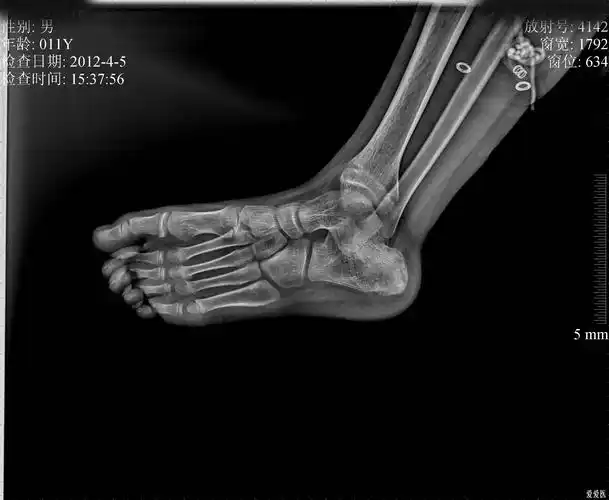

请会诊男孩右足跟疼痛3天

跟骨骨折后脚跟的x光片